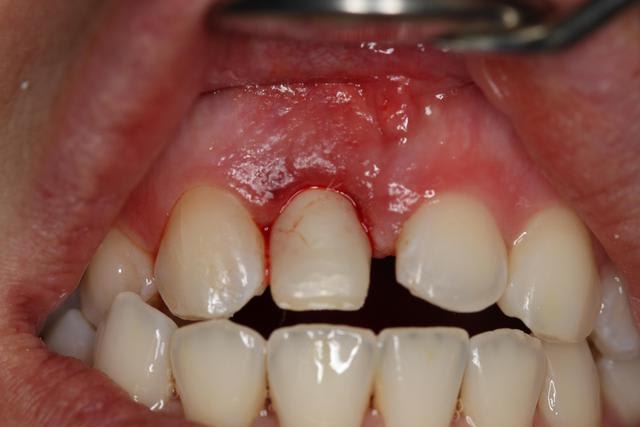

- 11 : extraction et implantation 11 rhyzalysée et mobile

- 21 : céramique pure sur 21.

Espaces mesio distaux : 8mm

Pas de recouvrement, occlusion inversée secteur 1/4, bout a bout incisif.

pour EII avec MCI, çà m'a l'air d'être une bonne indication. Le biotype gingival a l'air sympa...